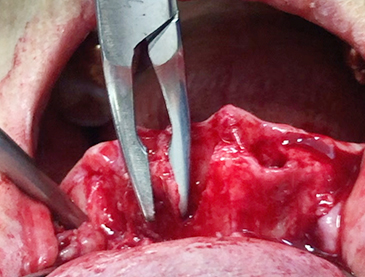

• Alveoloplasty (Posterior teeth) 1